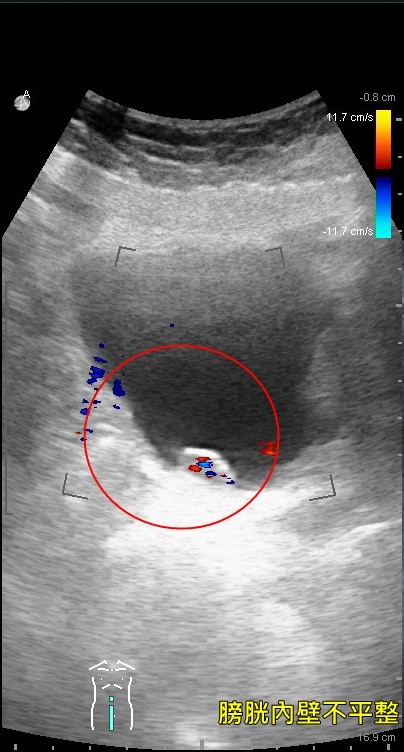

▲膀胱超音波顯影中,患者膀胱內壁不平整,多處長有腫瘤。(圖/亞洲大學附屬醫院提供)

但患者前來就醫時,表達下腹部並無疼痛感,當下研判應與腎結石無關,於是安排膀胱超音波檢查,透過膀胱鏡確診,發現膀胱竟有多處腫瘤,所幸腫瘤僅侷限於黏膜層,經採取「尿道膀胱腫瘤刮除術」,患者才免除無痛性血尿之苦。